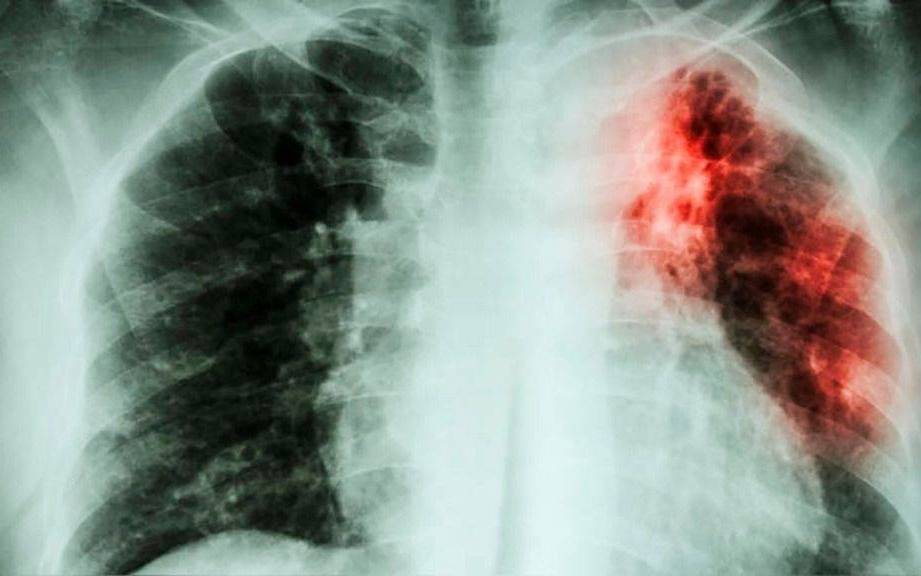

El brusco y preocupante aumento de casos de turberculosis en la Argentina, que se incrementó en un 38 por ciento respecto al promedio registrado en los diez años anteriores, en situaciones que las fuentes médicas relacionan a la caída en las tasas de vacunación y al debilitamiento integral de los sistemas de salud, debiera obligar a las autoridades sanitarias a promover medidas eficaces para revertir este alarmante repunte.

Como expuso el Boletín Epidemiológico Nacional, a mediados de abril pasado se habían notificado ya 3.488 nuevos casos de tuberculosis en el país, una cifra que supera ampliamente la mediana de los cinco años previos, que era de 2.530. Este incremento no es un hecho aislado: refleja una tendencia creciente que se viene consolidando desde hace más de una década, y que se aceleró tras la pandemia de Covid-19.

La tuberculosis es una enfermedad infecciosa causada por el bacilo de Koch que se transmite a través del aire al toser, estornudar o hablar. Afecta principalmente a los pulmones, pero puede comprometer otros órganos. Y aunque es prevenible y curable, sigue siendo un problema de salud pública, especialmente en contextos de hacinamiento, pobreza o acceso desigual a la salud.